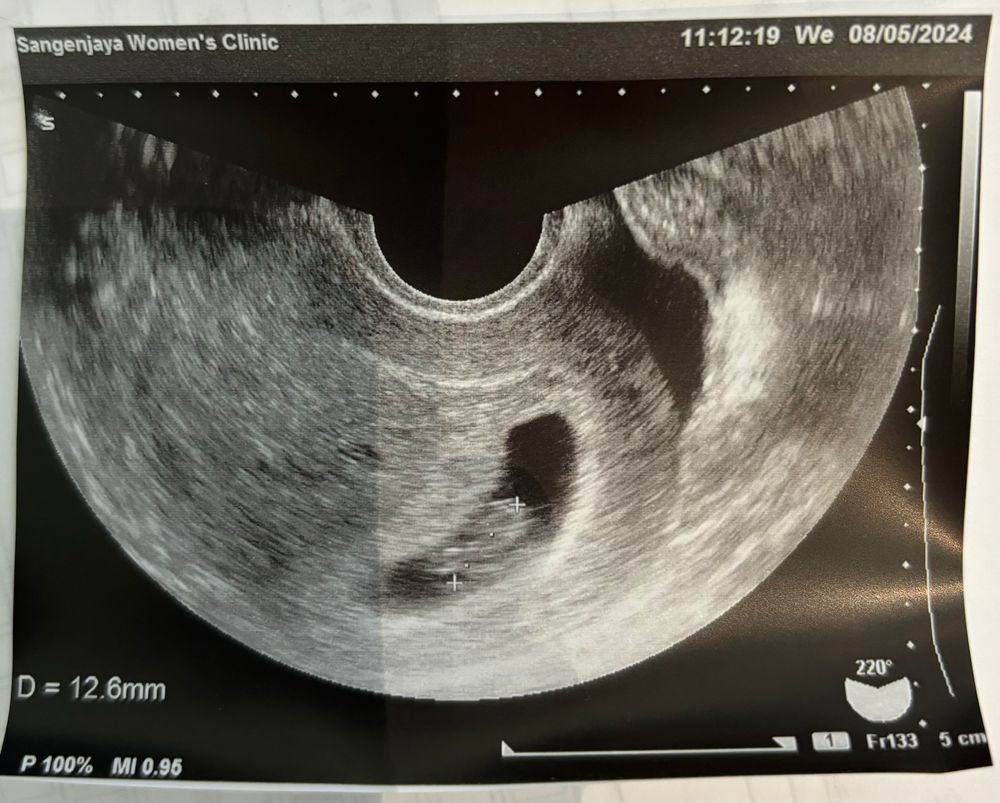

Результаты УЗИДорогие экошечки! Уже не знаю, что и делать. 7 неделя идет - мажет и все! Раз в день точно коричневые выделения разной степени интенсивности да есть. Ничего не тянет, токсикоз в полном наборе.

◼︎ По узи врач не видит причин для беспокойства: эмбрион растет согласно сроку, сб есть.